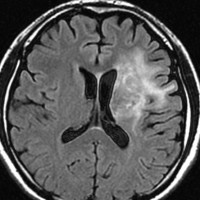

放射線治療後7週目

フレア画像です。腫瘍サイズが増大しています。もともと腫瘍周辺浮腫はなかったのですが大脳基底核と視床に浮腫が出現しています。スード・プログレッションの始まりです。